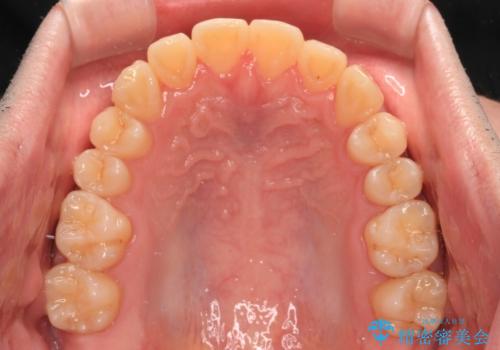

【モニター】前歯のデコボコとクロスバイト ワイヤー矯正で短期間に仕上げる

- 前歯のデコボコとクロスバイトを気にして来院された患者様です。

インビザラインでもワイヤー装置でも矯正治療は可能でしたが、煩わしい自己管理なしに短期間で治療を行いたいとのことで、目立たないワイヤー装置にて治療を行うこととしました。

- 1年1ヶ月